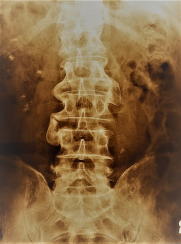

椎間板の消失 骨変形に伴う弯曲(1) (2) カルシウムの沈着

腰痛はもちろん、下肢のしびれ・筋力・感覚低下・麻痺・膝の変形などの他、排尿・排便障害に至ります。

これらのレントゲン写真のような人は程度に差はあれ、60代後半の人に多く見受けられている状態です。